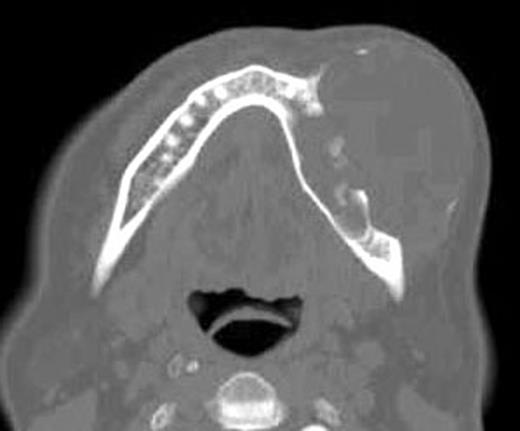

The clinical, radiolological and tomography signs (Fig. 3) evoke the hypothesis of a KCOT or ameloblastoma. An incisional biopsy and cytological smears were done and the results showed thin epithelial layer, composed of from 8 to 10 cell. The basal layer shows palisade organized cells with a uniform nucleus. In the direction of the cyst lumen, there is parakeratosis with a focal zone created of orthokeratins. The palisading appearance of the basal cells was evident and confirms the diagnosis of KCOT.